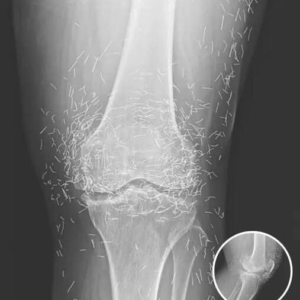

Doctors Stunned After Looking At This X-Ray Of Woman Suffering Joint Pain

A 65-year-old woman in South Korea experienced a shocking medical discovery when doctors found hundreds of tiny gold needles embedded in her knee tissue during a routine…